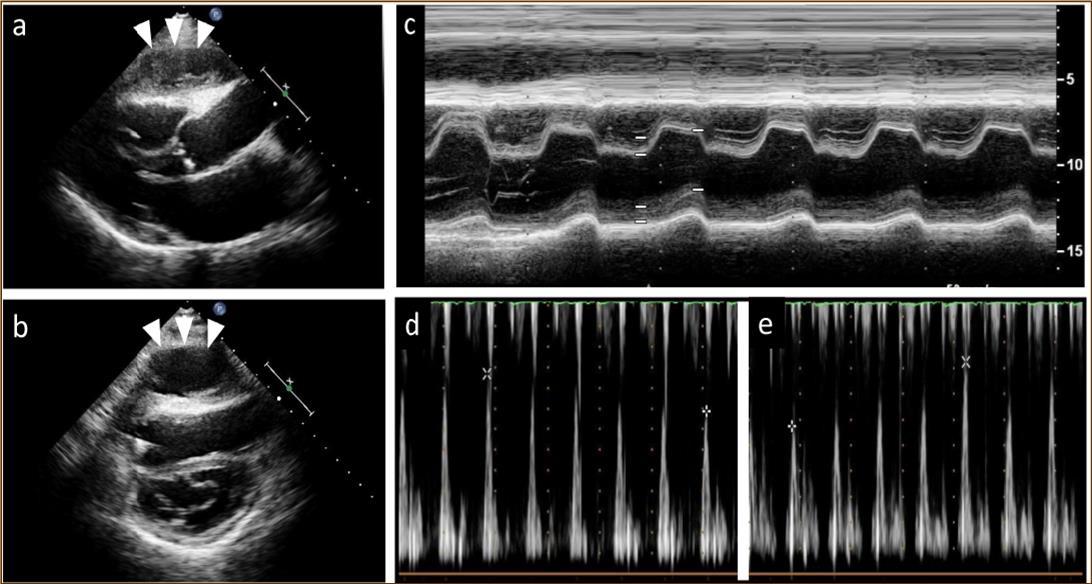

At 2 years post-HTx, when the patient first developed ACR, echocardiography revealed mild pericardial effusion, but there was no deterioration in hemodynamic parameters compared with the findings noted on previous examinations. ACR was considered as the cause of mild pericardial effusion and the dose of immunosuppressive regimens were increased. Two months after that, pericardial effusion persisted even though resolution of ACR was confirmed on EMB. At 2.5 years post-HTx, echocardiography revealed paradoxical septal motion and a large cystic-like mass with a thick capsule adhered to the right ventricle (Figure 1a, b). Roughly from that time, the patient began to experience dyspnea on mild exertion and lower leg edema. Oral diuretics were added to the prescription to relieve symptoms but dyspnea and edema did not resolve entirely.

Figure 1.Echocardiography findings. A large cystic-like mass with a thick capsule was found in front of the the right ventricle (white arrows) (a. long axis view; b. short axis view). Paradoxical septal motion were seen in a motion mode image of left ventricle (c). Respiratory variation in both mitral (d) and tricuspid inflow velocities (e) were seen.

Echocardiography findings. A large cystic-like mass with a thick capsule was found in front of the the right ventricle (white arrows) (a. long axis view; b. short axis view). Paradoxical septal motion were seen in a motion mode image of left ventricle (c). Respiratory variation in both mitral (d) and tricuspid inflow velocities (e) were seen.

At the age of 52 years, the patient was admitted to our institution for both evaluation of heart failure and regular right heart catheterization including EMB. With respect to allograft rejection, ACR was again detected on regular EMB, and the immunosuppressive regimens were strengthened. Further echocardiographic investigations were conducted to explore the implications of findings indicative of constrictive physiology with thickened pericardium. Respiratory variation in both mitral and tricuspid inflow velocities was seen, but these findings did not meet the complete criteria for CP diagnosis (Figure 1c-e). Magnetic resonance imaging of the heart revealed seroma and a thick cystic-like capsule tightly adhered to the right ventricle (Figure 2a, b). Right heart catheterization revealed elevation of right atrial pressure with severely reduced cardiac index (Figure 3a). The classic dip-and-plateau pattern of right ventricular diastolic pressure and equalization of right atrial pressure and right ventricular diastolic pressure were also observed (Figure 3b). Based on these results, effusive CP or cardiac tamponade-like hemodynamics were strongly suspected, although the etiology remained unknown. Therefore, at 3 years post-HTx, the patient initially underwent removal of the seroma through exploratory lateral thoracotomy to elucidate the etiology of the disease. Yellowish fluid was found and the fluid was completely aspirated. Immunosuppressive regimens including everolimus, which may interfere wound healing, were temporarily converted to standard three-drug regimens. Removal of the seroma via lateral thoracotomy did not lead to improvement in symptoms or hemodynamics. Pathological analysis revealed fibrin and seroma, but no malignant cells or infection. Since the initial procedure did not have any effect on the patient’s symptom, pericardiectomy through median sternotomy was performed at two months after the initial procedure. Intraoperative findings indicated a thickened pericardium and effusion in front of the right ventricle. At first, after sternotomy and adhesiotomy, the tissue in front of the right ventricle, which appeared to be thickened parietal pericardium, was completely resected and the effusion fluid was removed. However, high central venous pressure (20 mmHg) persisted, resulting in a displacement of the left ventricle by the right ventricle. Therefore, additional tissue from the front of the right ventricle was excised, corresponding to diffusely thickened visceral pericardium and epicardium. After the procedure, central venous pressure decreased from 20 to 10 mmHg, and displacement of left ventricle resolved. Pathological analysis of the resected tissues demonstrated chronic fibrosis and chronic inflammation with plasma cells, but no infectious etiology was identified (Figure 4 a, b). After the pericardiectomy, hemodynamics (Figure 3a, c) and symptoms improved, and the patient is currently experiencing a favorable clinical course without complications.